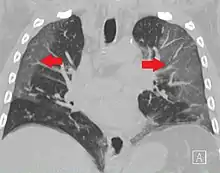

High-resolution CT image showing ground-glass opacities in the periphery of both lungs in a patient with COVID-19 (red arrows). The adjacent normal lung tissue with lower attenuation appears as darker areas.

Ground-glass opacity is among the most common imaging findings in patients with confirmed COVID-19.[16][17] One systematic review found that among patients with COVID-19 and abnormal lung findings on CT, greater than 80% had GGOs, with greater than 50% having mixed GGOs and consolidation.[16] GGOs with mixed consolidation has most often been found in elderly populations.[18] Several studies have described a pattern among initial, intermediate, and hospital discharge imaging findings in the disease course of COVID-19. Most commonly, initial CT imaging reveals bilateral GGOs at the periphery of the lungs. During initial stages, this is most often found in the lower lobes, although involvement of the upper lobes and right middle lobe has also been reported early in the disease course.[16][18] This is in contrast to the two similar coronaviruses, SARS and MERS, which more commonly involve only one lung on initial imaging.[19][20] As the COVID-19 infection progresses, GGOs typically become more diffuse and often progress to consolidation.[11][18] This is sometimes accompanied by the development of a crazy paving pattern and interlobular septal thickening.[18] In many cases the most severe pulmonary CT abnormalities occurred within 2 weeks after symptoms began.[17] At this point, many individuals begin showing resolution of consolidation and GGOs as symptoms improve. However, some patients have worsening symptoms and imaging findings, with further increase in septal thickening, GGOs, and consolidation. These patients may develop lung "white-out" with progression to acute respiratory distress syndrome (ARDS) requiring treatment escalation.[17][21]